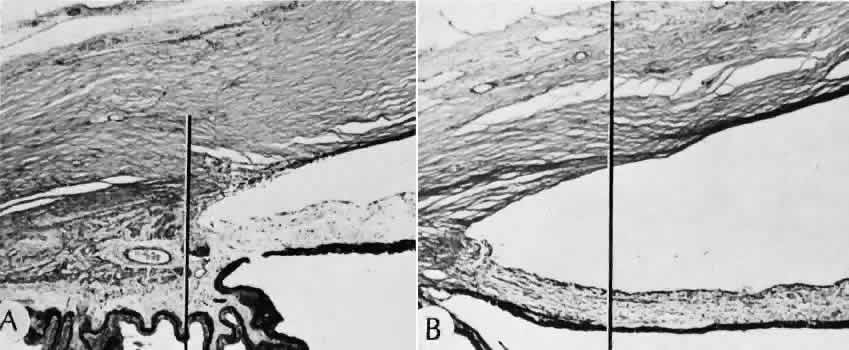

Healing at the site of a limbal surgical incision involves a combination of the features of repair of the cornea, conjunctiva, and sclera (see Fig. 5). Conjunctival epithelium will heal over an area of granulation tissue originating from the substantia propria of the conjunctiva and the episclera. The granulation tissue seals the wound if the wound edges are well apposed. The remainder of the healing process is similar to the healing of an external scleral wound. Granulation tissue is not formed in the internal portion of the wound because the uveal tract is not involved. The internal wound is healed by endothelial migration and reformation of Descemet's membrane in a manner outlined above for full-thickness corneal wounds.34,35

Because of the lack of blood vessels, the rate of wound healing is slow relative to that of the skin. Whereas an injury to the skin may have regained its tensile strength in 7 to 10 days, injuries to the surgical limbus may require as long as 12 months to regain a stable tensile strength. The tissues of the wound remain structurally weaker than the surrounding uninjured tissue (Fig. 9). The healing of a clear corneal cataract incision proceeds as described above.

Fig. 9. A. Well-healed scar (between arrows) barely perceptible in photomicrograph. B. Higher magnification of scar. Migrating corneal endothelium has closed the posterior hiatus of the wound in Descemet's membrane (arrow). (Hematoxylin-eosin stain; A, × 33; B, × 82.)